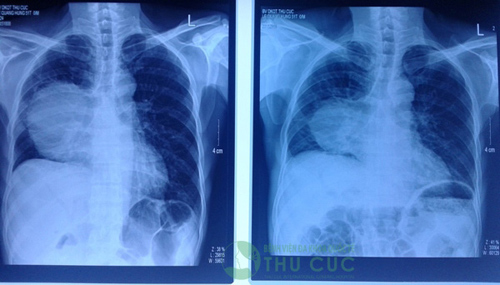

Trường hợp của bà V.T.H bị ung thư phổi giai đoạn muộn, khối u lan kín phổi khiến người bệnh không thở được. Sau 5 tháng điều trị với bác sĩ Lim Hong Liang tại Bệnh viện Thu Cúc, khối u gần như biến mất, người bệnh thở được bình thường, sức khỏe tốt.

Bệnh nhân L.Q.H, 51 tuổi sau 1 đợt điều trị, khối u đã giảm đáng kể.